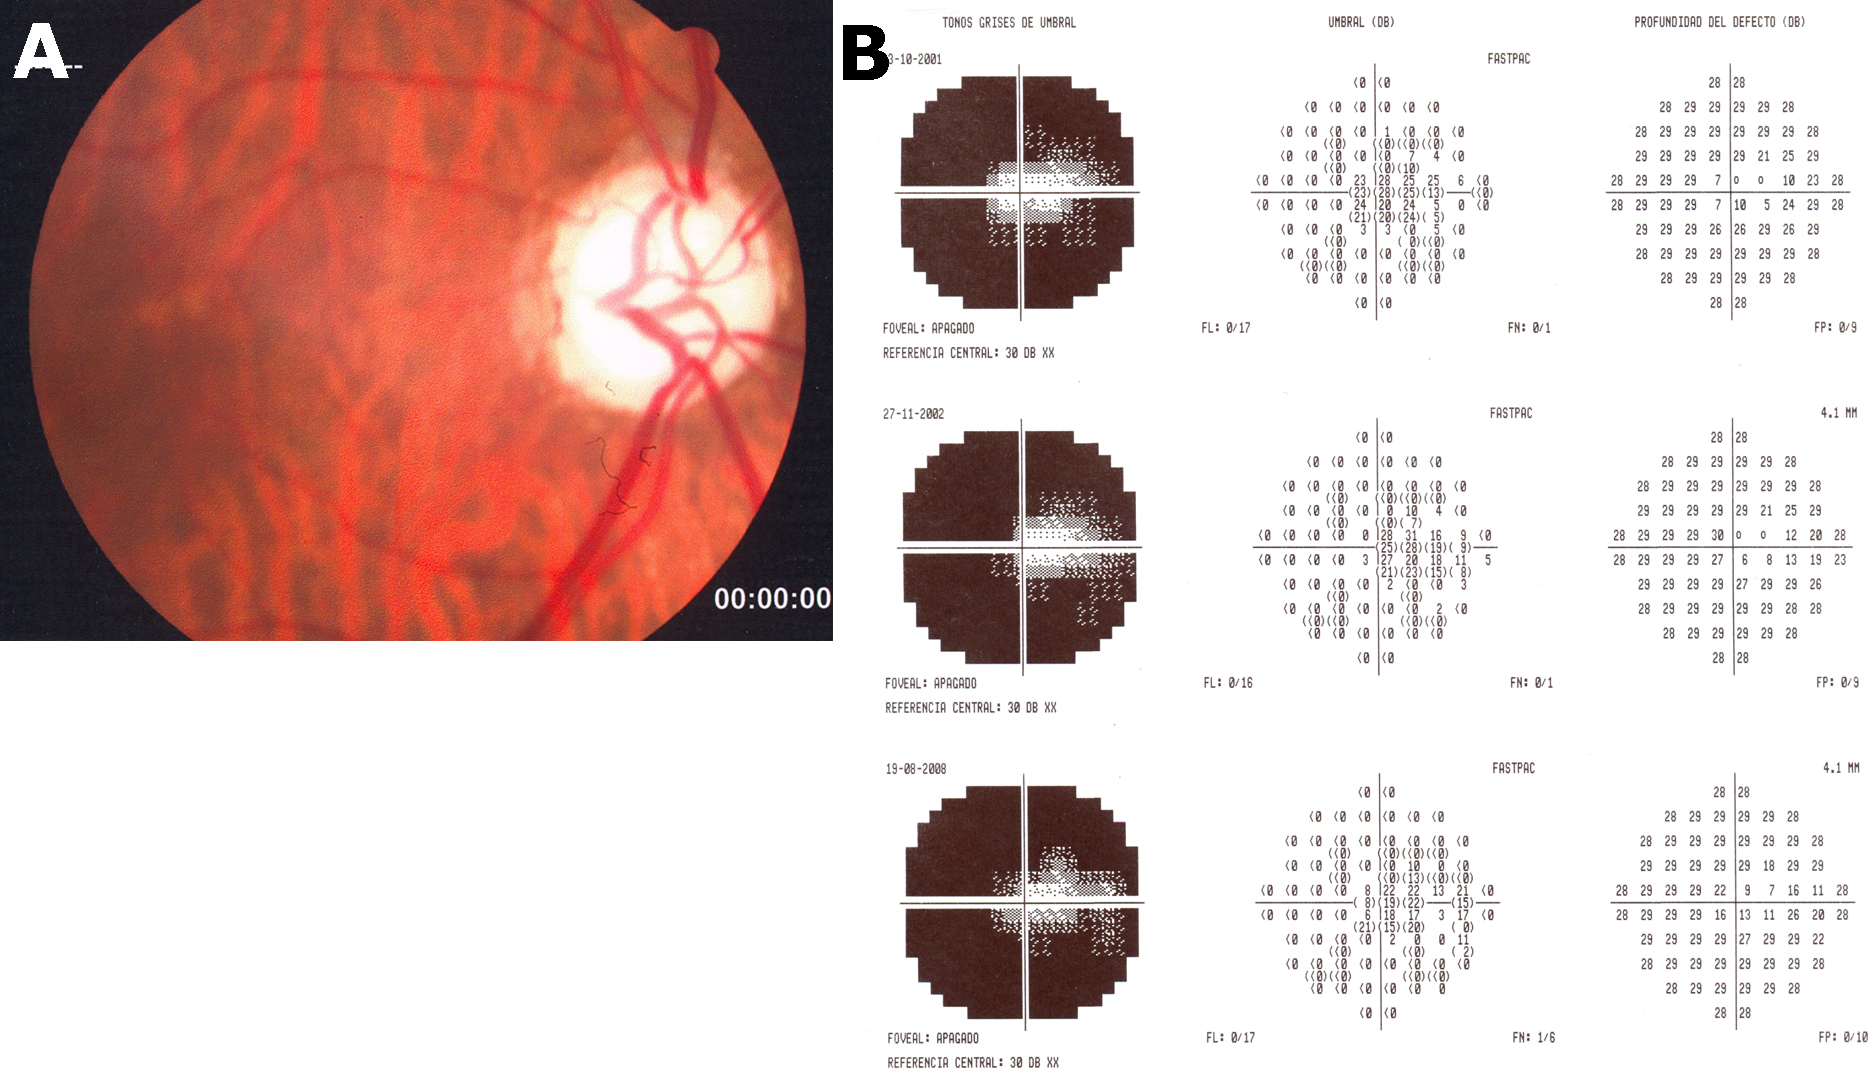

Field Of View (2) Discography: Vinyl, CDs, & More | Discogs。Molecular Vision: Romero, Mol Vis 2011; 17:1929-1939. Figure 3。Irving advertising former Texas Stadium site for major。View from the Vault, Volume Two - Wikipedia。・view/あの時の中で僕らは(サンプル版)×1・view/迷わないで(正規版)×1●状態:新品・未開封●カバー:あり●ヤケ:なし●ヨレ:なし●スレ:なしグッズ種類···その他#FIELDOFVIEW#FIELD_OF_VIEW#浅岡雄也